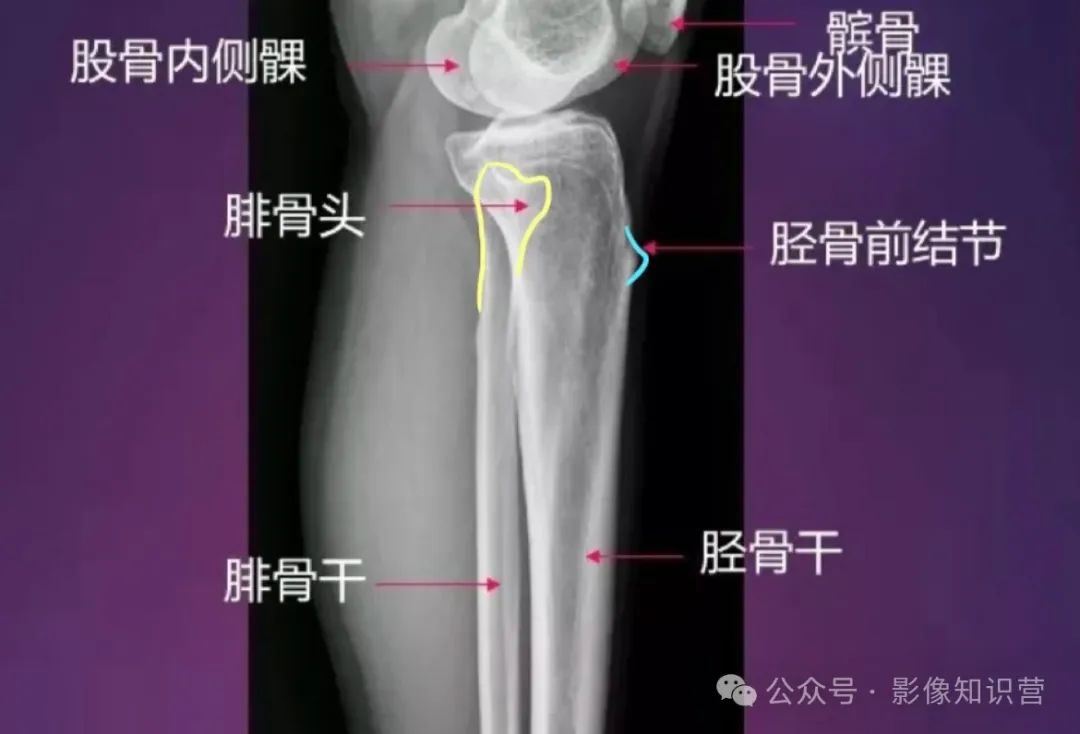

膝关节骨骼组成:股骨远端、胫骨近端、髌骨。

影像特征:X线侧位:观察髌骨位置及关节间隙(正常约3-5mm)。MRI可评估半月板(内“C”形、外“O”形)、交叉韧带及软骨损伤。

胫骨:位于小腿内侧,是小腿主要的负重骨。胫骨上端膨大,有内侧髁和外侧髁,两髁之间有髁间隆起。胫骨体前缘锐利,下端内踝是重要的体表标志。

腓骨:位于小腿外侧,较细。上端为腓骨头,下端为外踝,外踝比内踝略低。

股骨:是人体最长最结实的长骨。股骨头呈球形,与髋臼构成髋关节。股骨颈与股骨干之间形成颈干角。股骨体后方有粗线,是肌肉附着处。股骨下端有内侧髁和外侧髁,与胫骨和髌骨相关节。

解剖标志:股骨头、股骨颈、大转子、小转子、股骨干、股骨髁(内、外侧髁)。